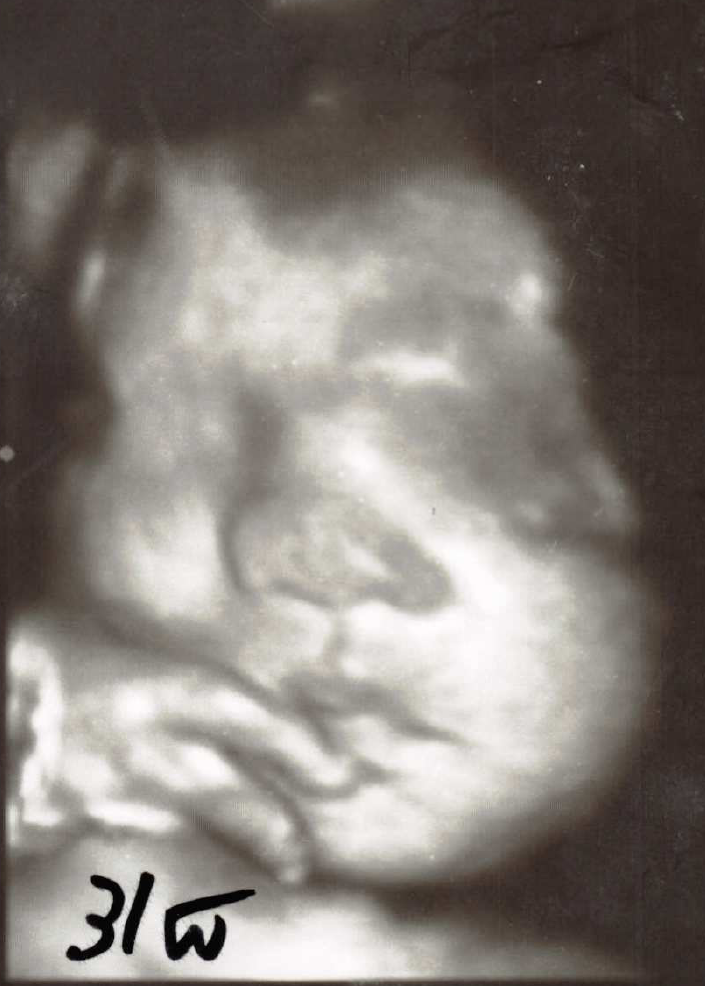

31週

妊娠中期以降になると、顔立ちが良く見えます。

7~8か月以降になると、特に、ふっくらした可愛い顔立ちが見えます。